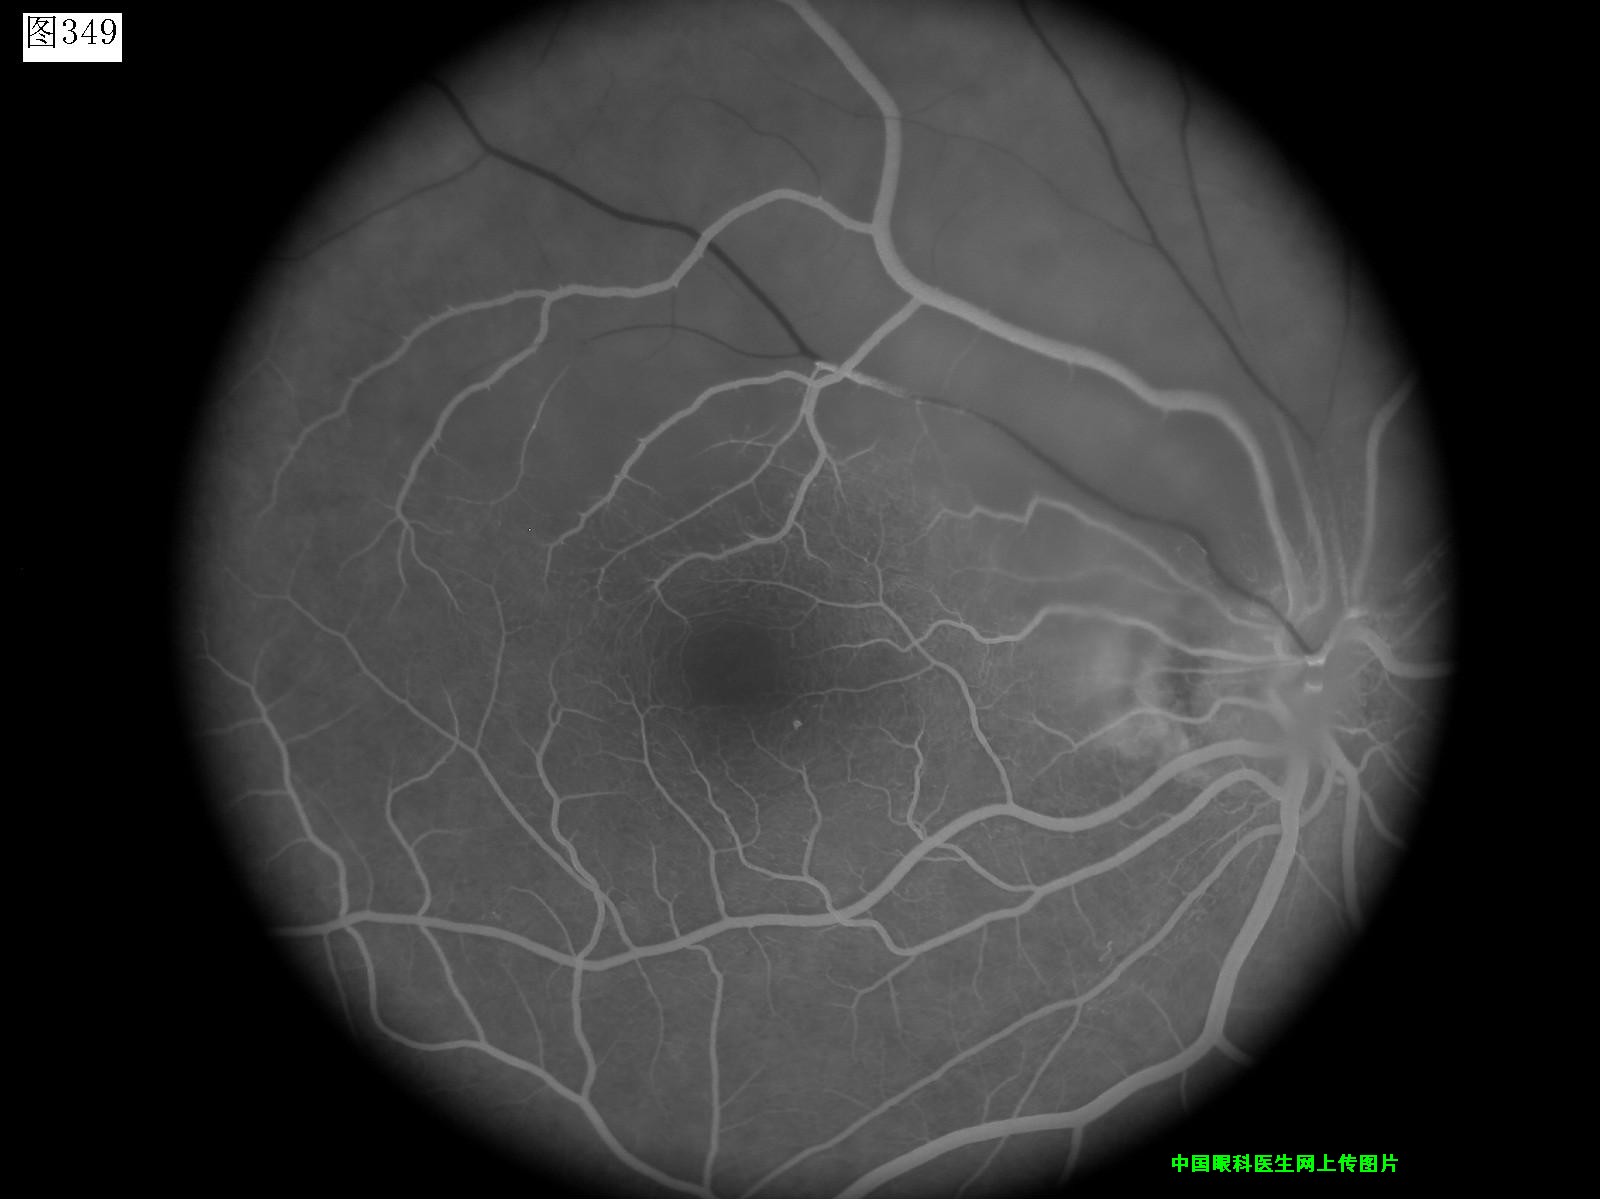

349 350 351 352